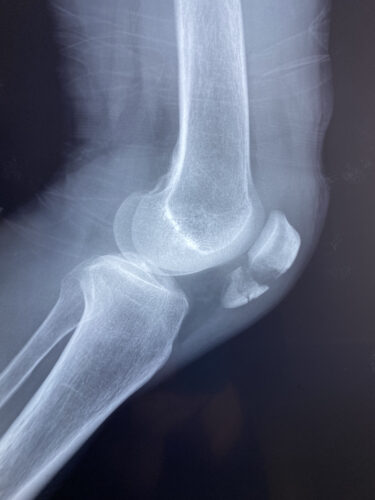

第24回整骨研究会「賜恩」研修会開催

春日部市市民活動センター(肘関節脱臼)

肘関節前方脱臼の1症例について